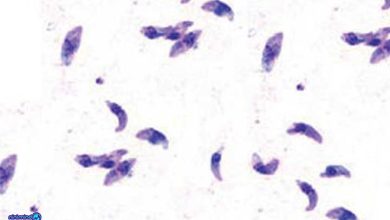

-  نوزاد  توکسوپلاسموزتوکسوپلاسموز یک عفونت انگلی است که بین انسان و حیوانات مشترک میباشد. این عفونت به دنبال انگل توکسوپلاسما گوندی ایجاد… بیشتر بخوانید »